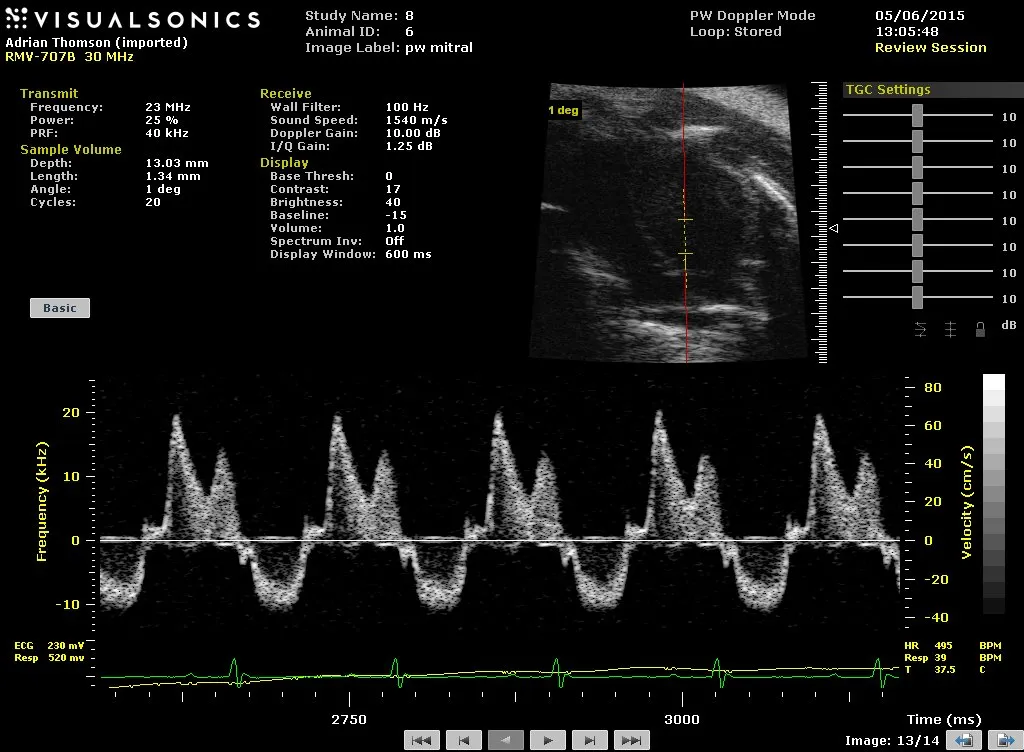

Mouse

Spectral Doppler blood flow from normal adult mouse heart showing in-flow and out-flow of blood from 4-chamber view of normal mouse heart – image